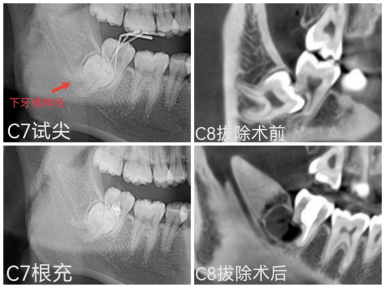

CBCT影像显示患者C7远中牙根吸收至根分叉处;C8为近中完全骨埋伏阻生牙,整颗牙齿完全在牙槽骨内,同时向前顶着邻牙C7的远中牙根致牙根吸收,且三颗牙根分叉、弯曲程度较大,牙根与右侧下颌管之间无骨质间隔(牙齿压迫下牙槽神经),因此拔除难度高,存在下牙槽神经损伤风险。

综合评估后,梁燕立即启动多学科联合诊疗(MDT),由口腔颌面外科、口腔正畸科、牙周黏膜科、口腔修复种植科MDT团队成员对患者病情进行详细充分地讨论,并综合患者及家属意愿,选择了“保留天然牙C7、拔除C8阻生牙”治疗方案。首先由口腔颌面外科主治医师陈友利完成C8阻生牙拔除手术,整个过程无痛,最大程度保护了邻牙C7牙周组织并保留了牙槽骨,规避了下牙槽神经损伤,减轻了患者疼痛、肿胀等术后反应。同期由牙体牙髓科主任医师梁燕、主治医师叶韵瑶对C7外吸收的远中牙根进行显微根尖手术于外吸收部位清创并切除根尖,应用生物陶瓷材料行远中根尖屏障术,封闭并完善根管治疗。最后由口腔修复种植科主治医师孟茂花完成C7冠修复治疗。